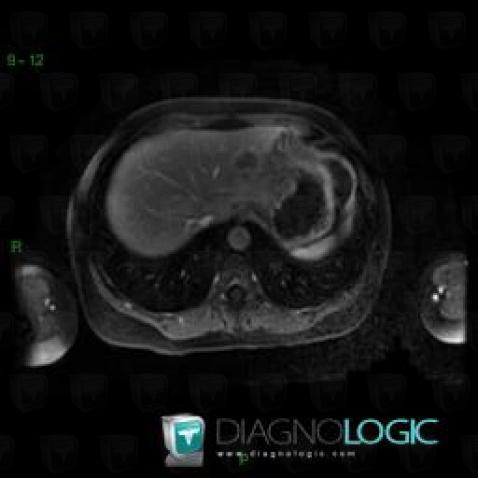

Focal fatty change, Liver, MRI

Here is the specific information in the key image above:

- Diagnosis Focal fatty change, Location(s) Liver, with gamuts Low density in portal phase hepatic lesion